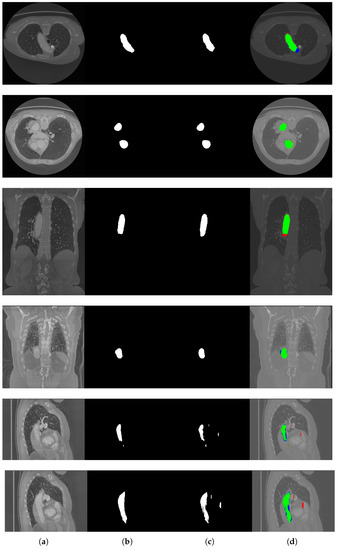

After pre-processing, CT scans were cropped to reduce their size. This also allowed one to remove parts of the scan where the aorta was not present (normally, the entire scan goes from the pelvis to the head). The dimensions of the 3D bounding box were multiples of 32 (to have a final image size that fit the input of the chosen segmentation network without using padding). Finally, the slices for each view (coronal, sagittal and axial) were extracted and used for network training. An example of an axial slice together with its label is given in Figure 3.

Figure 3.

An axial slice together with its label obtained after pre-processing.